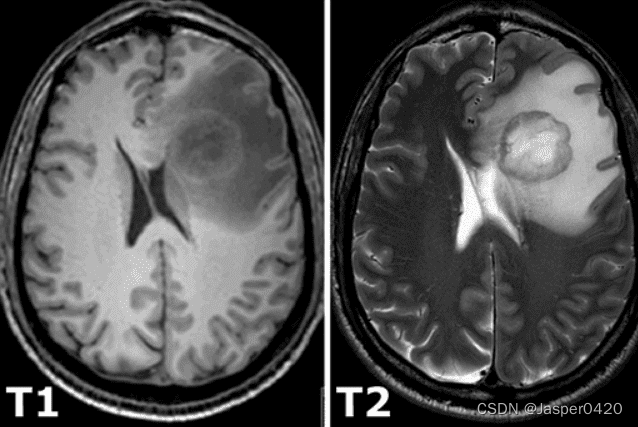

所有的恒定磁化被一个额外的射频脉冲旋转到另一个平面,该脉冲足够强,应用时间足够长,以使磁化倾斜。激发之后,磁化就立即在另一个平面上旋转起来。旋转的磁化在接收线圈中产生了MR信号。然而,由于两个独立的过程,MR信号迅速消失,这两个过程减少了磁化,从而导致恢复到激发前的稳定状态,产生所谓的T1图像和T2磁共振图像。T1松弛与核子对其周围的能量过剩有关,而T2松弛指的是个别磁化矢量开始相互抵消的现象。上述现象是完全独立的。因此,不同的强度代表不同的组织,如下图所示。